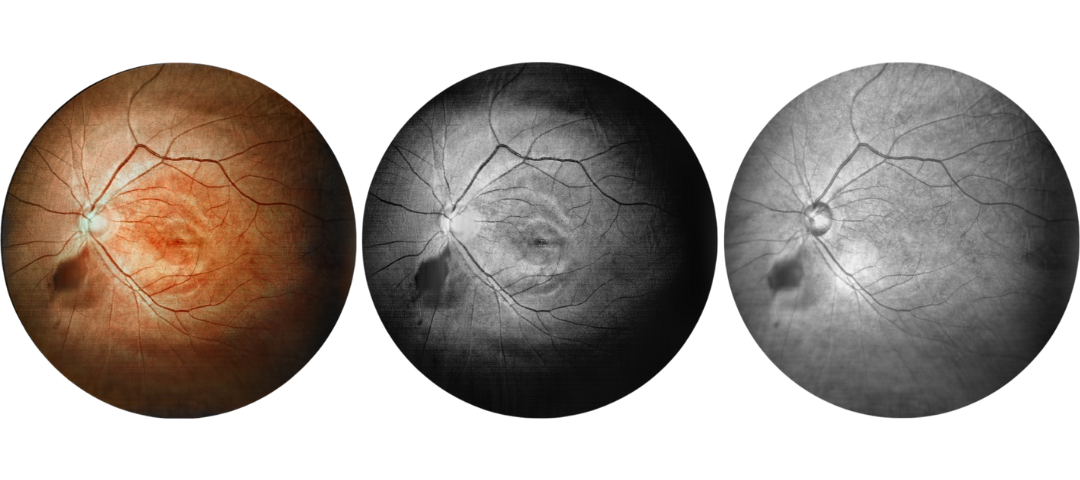

Fundus Cases Display

Our SLO makes fundus examination easier for you, capturing ultra-clear and wide-angle images of the retina and choroid, and then synthesizing color fundus images to present a rich picture of the fundus status.

Diabetic retinopathy: bleeding and microvascular lesions

Diabetic retinopathy: bleeding

High blood pressure, venous obstruction, and bleeding